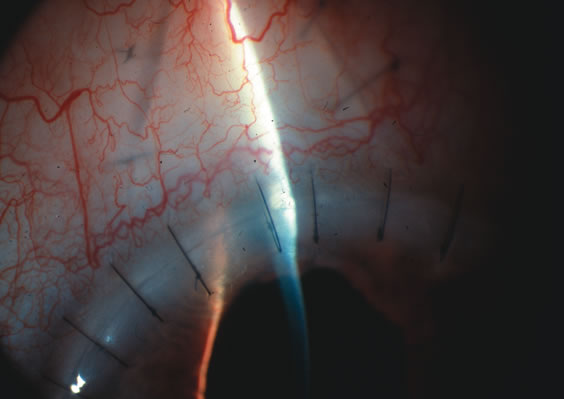

CATARACT EXTRACTION ALONE REDUCES IOP IN MOST EYES WITH ANGLE-CLOSURE GLAUCOMA

Uncomplicated cataract extraction substantially reduces IOP, along with the number of postoperative glaucoma medications in eyes with angle-closure glaucoma.146,147 When preoperative gonioscopy reveals PAS, along with adjacent areas of appositional closure, lens extraction alone in select cases may be a reasonable alternative to filtration surgery.148,149 Phacomorphic angle-closure disease due to enlargement of the lens with progressive angle crowding is eliminated following lens extraction. The width and depth of the anterior chamber angle in eyes with angle-closure glaucoma increases significantly after cataract extraction with IOL implantation and becomes similar to open-angle glaucoma and normal eyes.150,151 (Fig. 5). Combining phacoemulsification, IOL implantation, and limited goniosynechialysis is effective in the treatment of cataract and chronic angle-closure glaucoma.152 Phacoemulsification with implantation of a foldable IOL is more effective in reducing IOP and improving visual acuity than surgical peripheral iridectomy in eyes with acute angle-closure glaucoma.153

Fig. 5. Anterior chamber angle changes associated with lens extraction and PCIOL This 65-year-old Vietnamese woman has a long-standing history of chronic angle-closure glaucoma treated with laser peripheral iridectomy. The optic nerve demonstrated mild glaucomatous damage and IOP was moderately controlled on two antiglaucoma medications. The cataract was removed through temporal clear corneal phacoemulsification with foldable acrylic IOL. A. Symptomatic cataract in narrow-angle glaucoma eye with patent iridectomy. B. Intraoperative goniophotograph showing crowding of angle with increasing narrowness due to phacomorphic component. C. Intraoperative photograph showing temporal clear corneal approach with IOL in the capsular bag. D. Intraoperative goniophotograph demonstrating deepening of chamber angle following lens extraction. Proposed theories for IOP reduction following lens extraction with complete wound closure:

1. Anterior chamber deepening with improved access to trabecular meshwork

2. Increase in traction on the trabecular meshwork

3. Improved outflow facility mediated by an increase in prostaglandin release

4. Reduction in aqueous humor production

5. Atrophy of ciliary body processes

6. Goniosynechialysis due to intraoperative over deepening of AC with viscoelastic

7. Relief of undiagnosed pupil block